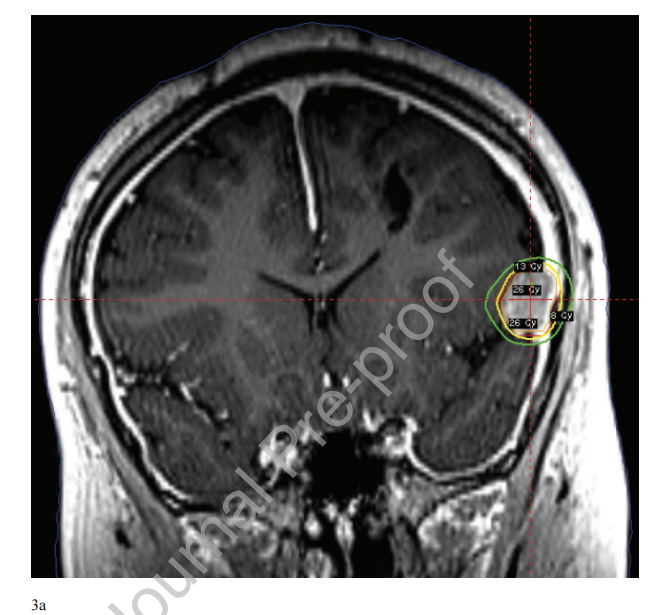

图3 (A) 14岁女性,影像学明确放射诱导脑膜瘤,接受单次放射手外科治疗。放射外科使用钴-60平台和可重新定位的面罩固定。按50%等剂量线照射13 Gy。橙色线为GTV,红色线为0.5mm PTV外扩,黄色线为13 Gy等剂量线,绿色线为8 Gy等剂量线。(B)该患者在放射外科治疗前11年曾因第四脑室复发性脉络膜丛乳头状瘤(33次59.4 Gy)分次照射IMRT治疗。辐射诱发的脑膜瘤区域受照在10-20 Gy之间。

没有已知的儿科数据评估在面罩治疗的情况下,SRS治疗的GTV到计划靶体积(PTV)的适当扩大。成人数据的外推是合理的,目的是使用较小的边际以尽量减少脱靶剂量。例如,成人数据表明,在具有实时高清运动管理(HDMM)系统的钴-60放射外科平台中,PTV为1mm(径向)和1.5 mm(上下)外扩是合适的。其他机构使用更小、均匀的1mm PTV边缘外扩,而额外的数据表明几何0.5 mm PTV外扩可能足以维持肿瘤覆盖。在缺乏儿科特异性数据的情况下,在接受清醒SRS治疗的儿童中,仔细的图像引导、严密的HDMM设置和使用尽可能小的PTV (0.5 mm外扩)是合理的(图3),这取决于当地设备的可用性和机构治疗方案。